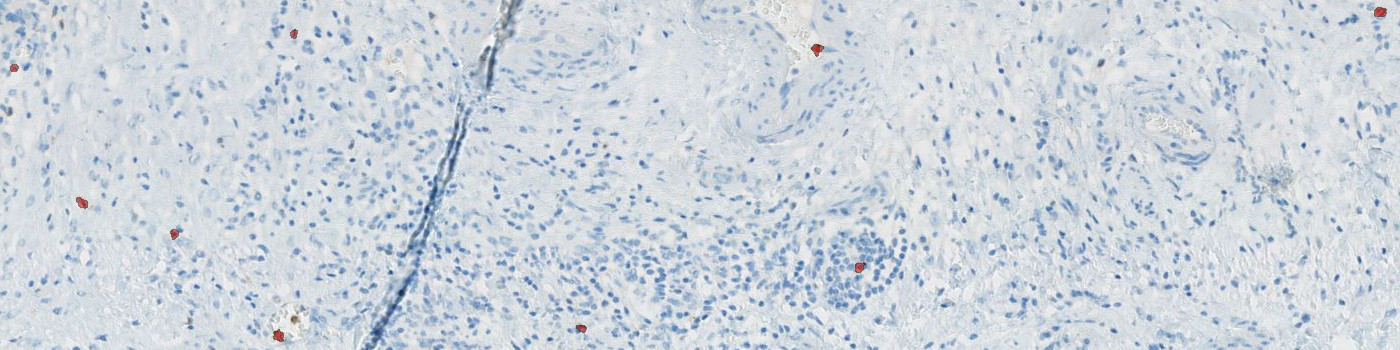

A NK positive cell is detected as a haematoxylin stained nucleus surrounded by DAB membrane stain. Initially, the protocol detects haematoxylin stained nuclei surrounded by brown stain using a poly blob filter on the H&E haematoxylin band and a median filter on the HDAB-DAB band. The DAB membrane stain is emphasized by a mean unsharp filter, thereby excluding blurry background stain. Then, positive nuclei are detected based on size, shape, and amount of surrounding DAB stain. Final NK cells are seen in FIGURE 2.